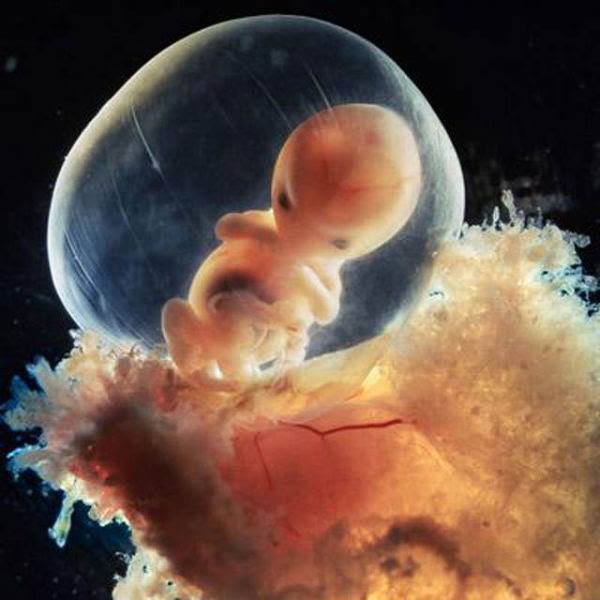

| 5 weeks.Approximately 9 mm.You can now distinguish the face with holes for eyes,nostrils and mouth |